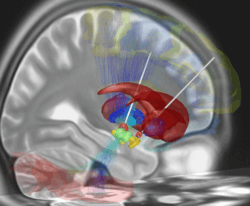

The deep brain stimulation system consists of three components: the implanted pulse generator (IPG), the lead, and the extension. The IPG is a battery-powered neurostimulator encased in a titanium housing, which sends electrical pulses to the brain to interfere with neural activity at the target site. The lead is a coiled wire insulated in polyurethane with four platinum-iridium electrodes and is placed in one or two different nuclei of the brain. The lead is connected to the IPG by the extension, an insulated wire that runs below the skin, from the head, down the side of the neck, behind the ear to the IPG, which is placed subcutaneously below the clavicle or, in some cases, the abdomen.[12] The IPG can be calibrated by a neurologist, nurse, or trained technician to optimize symptom suppression and control side-effects.[13]

DBS leads are placed in the brain according to the type of symptoms to be addressed. For non-Parkinsonian essential tremor, the lead is placed in the ventrointermediate nucleus (VIM) of the thalamus; for dystonia and symptoms associated with Parkinson's disease (rigidity, bradykinesia/akinesia, and tremor), the lead may be placed in either the globus pallidus internus or the subthalamic nucleus; for OCD and depression to the nucleus accumbens; for incessant pain to the posterior thalamic region or periaqueductal gray; for Parkinson plus patients to two nuclei simultaneously, subthalamic nucleus and tegmental nucleus of pons, with the use of two pulse generators; and for epilepsy treatment to the anterior thalamic nucleus.[14]

Deep brain stimulation represents an advance on previous treatments which involved pallidotomy (i.e., surgical ablation of the globus pallidus) or thalamotomy (i.e., surgical ablation of the thalamus).[52] Instead, a thin lead with multiple electrodes is implanted in the globus pallidus, nucleus ventralis intermedius thalami (Vim) or the subthalamic nucleus and electric pulses are used therapeutically. The lead from the implant is extended to the neurostimulator under the skin in the chest area.